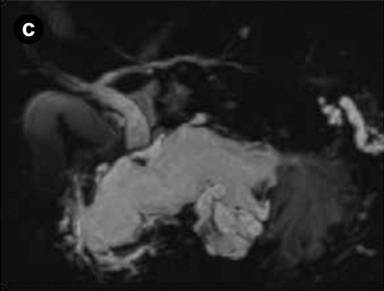

A 75-year-old man was admitted to the hospital because of acute onset of severe epigastric pain and body weight loss. On physical examination, palpable mass and tenderness of upper abdomen was noted. Laboratory studies revealed elevated C-reactive protein (7.0 mg/dL; reference range: 0-0.5 mg/dL), CEA (39.7 ng/mL; reference range: 0-5 ng/mL), CA 19-9 (62.3 U/mL; reference range: 0-37 U/mL) and HbA1c (13.2%; reference range: 3.4-5.8%). Results of complete blood count, plasma levels of electrolytes, tests of coagulation, amylase, lipase, kidney and liver function were within normal limits. Computed tomography (CT) and magnetic resonance imaging (MRI) of the abdomen showed a markedly dilated main pancreatic duct (45 mm), a papillary tumor (20 mm in diameter) protruding into the main pancreatic duct of the distal pancreas and splenic vein obstruction (Figure 1abc). On duodenoscopy with a lateral viewing of endoscope, mucus was discharged from the enlarged papilla of Vater (Figure 2a). Peroral pancreatoscopy was performed, revealing the papillary tumor on the main pancreatic duct (Figure 2b). Pathological examination of biopsy specimens of the tumor showed papillary mucinous adenoma (Figure 2c).

Figure1. a. Computed tomography (CT) showed a markedly dilated main pancreatic duct (45 mm, arrow) and splenic vein obstruction (arrowhead). b. CT showed a papillary tumor (20 mm in diameter) protruding into the main pancreatic duct of the distal pancreas (arrowhead). c. Magnetic resonance cholangiopancreatography (MRCP) showed a markedly dilated main pancreatic duct. |